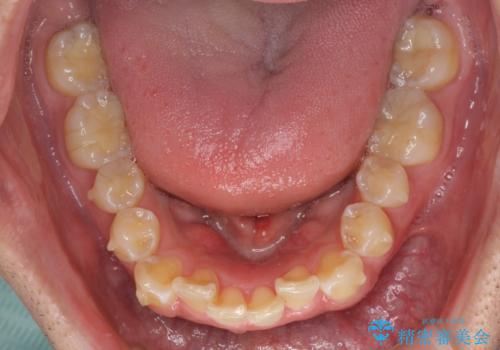

- 前歯のデコボコを強い咬みしめを気にして来院された患者様です。

インビザラインを用いて、前歯の叢生を解消するとともに、ディープバイトを改善していくこととしました。

ディープバイトが改善されたことで、顎への負担が軽減され、更には上顎前歯の突出感も改善することができました。

矯正治療後には欠けてしまった修復物をセラミックインレーにて修復治療しました。